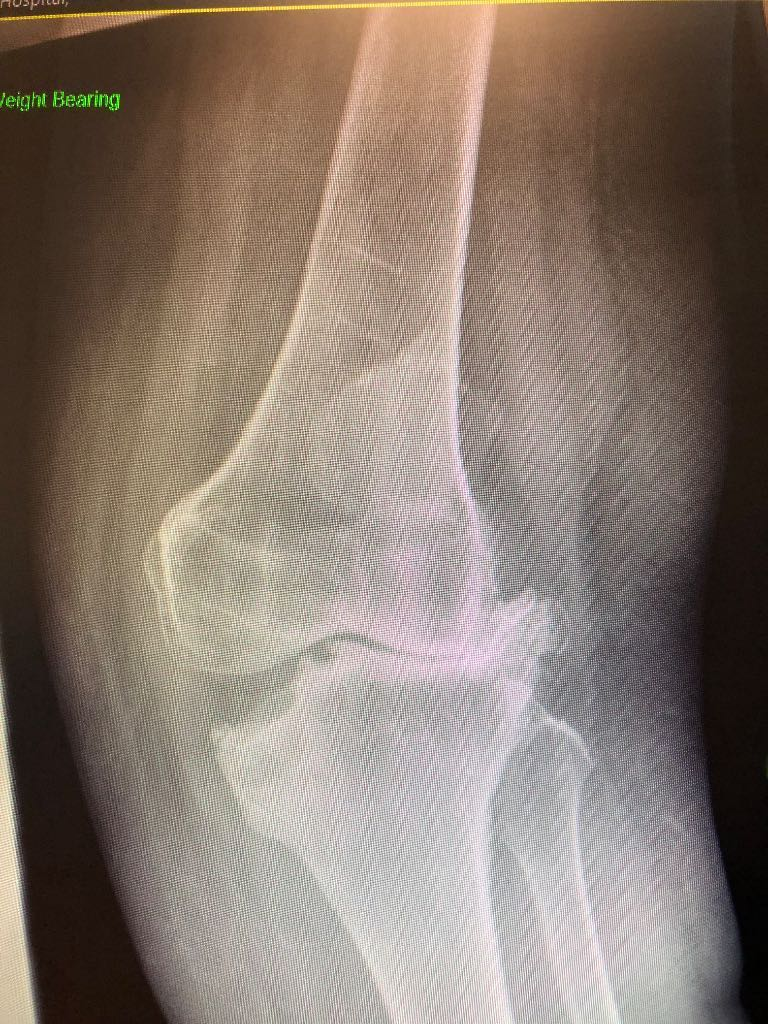

Tibial osteotomy - (5-50)

Mr Mughal is also highly experienced in deformity correction for both adolescents and adults, including knock knee, bow leg deformities and the complex condition known as miserable malalignment syndrome. He uses advanced computer based and 3D modelling techniques to plan personalised corrective surgery, aiming to preserve joints affected by early osteoarthritis. When combined with cartilage regeneration procedures, this approach enables him to offer a comprehensive and tailored treatment pathway.